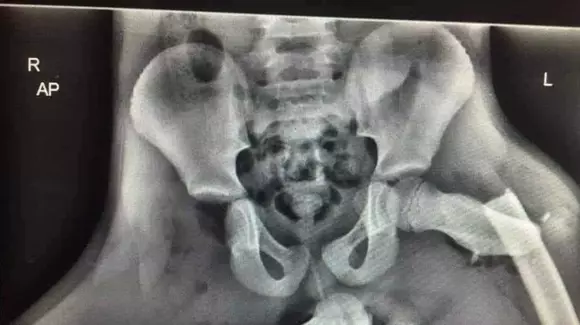

Probabil că toți pasagerii știu că este riscant să călătorească în dreapta ținând picioarele pe bordul mașinii. Nu de alta, dar mașinile nu par să fie proiectate pentru așa ceva, că nu au suport care să faciliteze această poziție. Însă unii pasageri o consideră mai comodă; sau fac asta din plictiseală. Motivul nu este important, ci riscul pe care și-l asumă făcând asta. Un risc exemplificat teribil de real în radiografia aceasta.

Nu trebuie să fii medic ca să-ți dai seama că ceva nu e în regulă cu poziționarea în imaginea de mai sus. Nici noi nu suntem medici, dar suntem convinși că femurul drept al acestui pacient este dislocat urât de tot, iar cel drept este rupt. Și, din nou, nu suntem medici, dar credem că această situație este îndreptată după multe luni de recuperare, asta dacă mai poate fi îndreptată.

Pacientul din imaginea de mai sus este o tânără din Wales, Marea Britanie, care a fost surprinsă ținând picioarele pe bord în momentul unui accident. La șocul impactului a participat și airbagul, iar poliția din Wales — care a și dat publicității această imagine, la începutul acestui an — a spus că traumele i-au schimbat viața tinerei. Bănuim că nu în bine.